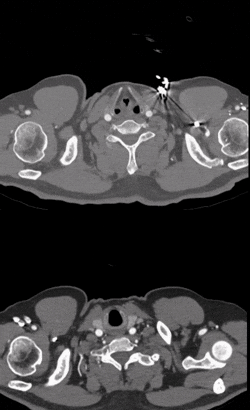

术前CTA横断面

Ⅲ型弓